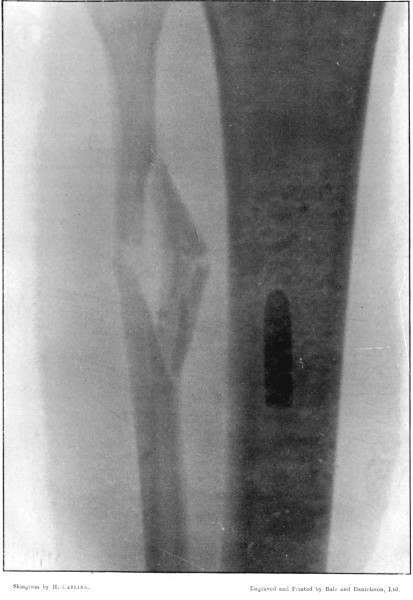

20. Transverse Fracture of the Tibia212

21. Puncture of the Tibia, with an Oblique Fissure214

22. Notched Fracture of the Tibia216

23. Punctured Fracture of the Fibula218

24. The same Fracture, Lateral View 220